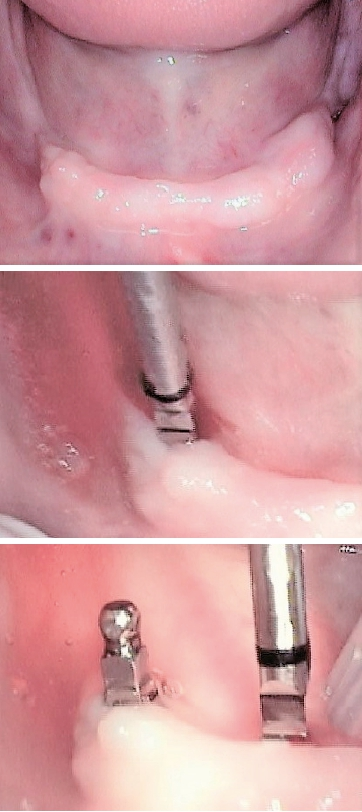

Im Unterkiefer greife ich auf vier einteilige Implantate (mit den Durchmessern 2,5 – 3,0 oder 4,0 mm) mit Kugelköpfen zurück, die jeweils vier Abflachungen der Kugel aufweisen. Deshalb habe ich diese in der Vergangenheit auch als „Tulpen“ bezeichnet. Der Grund für diese Abflachungen sind die O-Ringe der Matrize, die durch die Abflachung nicht schnell „ausleiern“ (durch tägliches Ab- und Wiedereingliedern der Prothese). Eine der abgeflachten Flächen sollte nach bukkal zeigen (siehe orangener Ring Abb. 7).

Im Unterkiefer inseriere ich daher i.d.R. immer vier einteilige Mini-Implantate in Sofortbelastung mit Einarbeitung der Matrizen in eine bereits harmonisch balanciert, okklusal eingestellte Prothese.